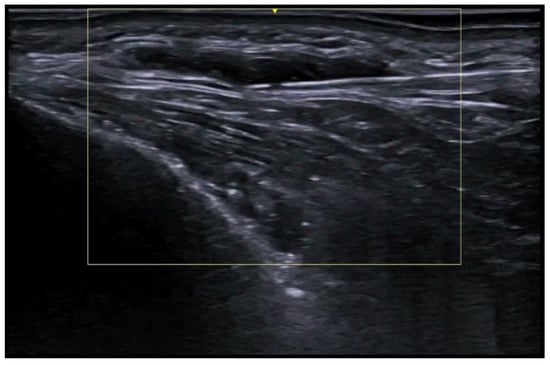

- Liu, Q.; Zhou, J.; Wang, W.; Chen, X.; Xu, Y.; Huang, H.; Mi, J. A prospective study of super-thin anterolateral thigh flap harvesting assisted by high-frequency color Doppler ultrasound in detecting perforators in deep adipose layers. Zhongguo Xiu Fu Chong Jian Wai Ke Za Zhi 2024, 38, 62–68. [Google Scholar] [PubMed]

- Hayashi, A.; Giacalone, G.; Yamamoto, T.; Belva, F.; Visconti, G.; Hayashi, N.; Handa, M.; Yoshimatsu, H.; Salgarello, M. Ultra High-frequency Ultrasonographic Imaging with 70 MHz Scanner for Visualization of the Lymphatic Vessels. Plast. Reconstr. Surg. Glob. Open 2019, 7, e2086. [Google Scholar] [CrossRef] [PubMed]

- Cowan, R.; Mann, G.; Salibian, A.A. Ultrasound in Microsurgery: Current Applications and New Frontiers. J. Clin. Med. 2024, 13, 3412. [Google Scholar] [CrossRef]

- Visconti, G.; Hayashi, A.; Bianchi, A.; Tartaglione, G.; Bartoletti, R.; Salgarello, M. Lymphaticovenular Anastomosis for Advanced-Stage Peripheral Lymphedema: Expanding Indication and Introducing the Hand/Foot Sign. J. Plast. Reconstr. Aesthetic Surg. 2022, 75, 2153–2163. [Google Scholar] [CrossRef]